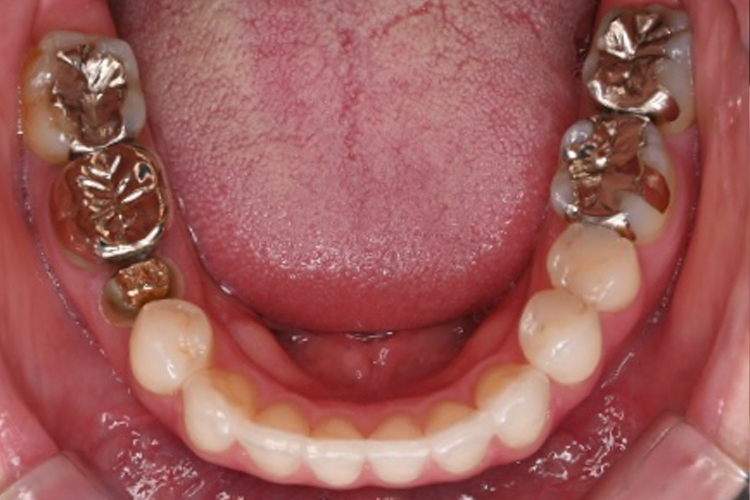

症例3

BEFORE

AFTER

| 主訴 | 銀歯を白くしたい。 |

|---|---|

| 治療内容 | オールセラミッククラウン・オールセラミックインレー |

| 治療のリスク | 仮歯代、根管治療代は別途かかります。 |